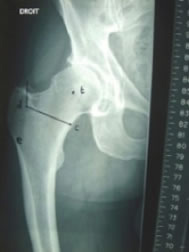

Post-op X-ray

As we have discussed many times slight varus stem positioning does not seem to make a clinical difference with neck stabilized stems.

A K2 mid-length stem was selected as an ideal choice in converting her to a total hip arthroplasty for three reasons. First, her prior fracture had compacted down as it healed, leaving her with a shortened offset and valgus neck that are better re-approximated with a modular prosthesis. Second, most modular primary systems do not provide extra length options, which was helpful in this particular case in bypassing the stress riser of her previous pin sites as well as strengthening the proximal one-third femur in this osteoporotic patient who has already demonstrated multiple fragility fractures and lessening her chance of a periprosthetic fracture in the future. Third, the simplicity of the K2 system allowed this case to be completed in about half an hour, whereas many modular systems (such as traditional S-ROM) require more preparation and operating time for milling out the proximal femur, etc. The Zweymueller geometry allowed a quick and rotationally solid fit in the osteoporotic bone. The patient was able to ambulate in the hallway that evening and confidently place full weight on the solidly seated stem.